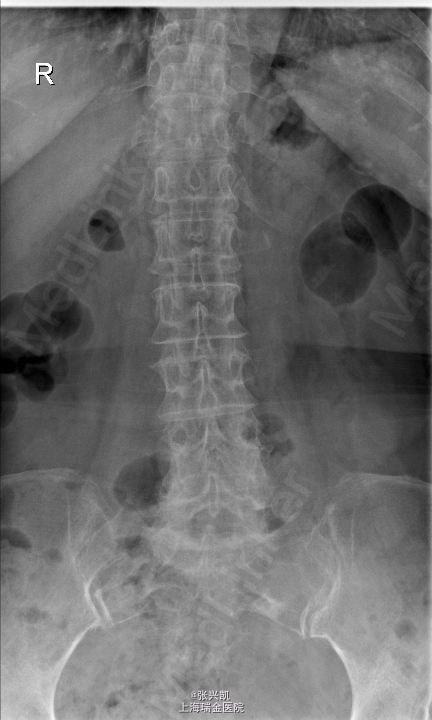

查体:脊柱无侧弯畸形,无叩痛压痛,上肢感觉肌力正常,双下肢疼痛,右侧较重,小腿前外侧感觉异常,下肢肌力4-5级,跟膝腱反射(+),巴氏征(-) 辅助检查:X线动力位示:L4椎体滑脱,腰椎退行性改变 MR:L4椎体向前I°滑脱,L3-5椎间盘突出,椎管狭窄

诊断:腰椎椎管狭窄L4-5 L4椎体滑脱 处理:腰椎后路减压复位融合内定术